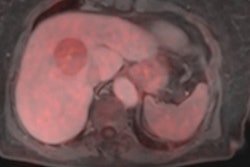

In the management of cancer patients, a gap exists between molecular understanding of cancer and its application in diagnostic methods to stratify patients based on established biomarkers, Austrian experts said. To boost understanding of disease mechanisms, better target identification and more progress in novel therapeutic approaches are vital, as well as greater multidisciplinary cooperation, they believe. Visit the Molecular Imaging Community, or click here.